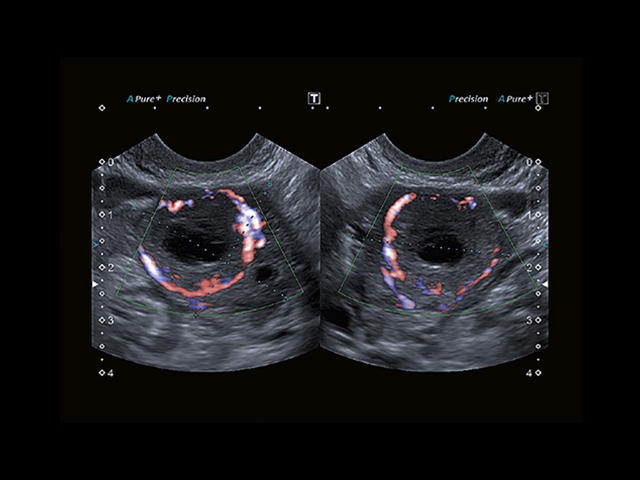

Aplio 500 – ультразвуковой сканер премиум класса, сочетающий в себе быстродействие диагностики и отличное качество визуализации. Более 30 датчиков на выбор, в т.ч. матричные, монокристаллические, 4D, эндоскопические для любых типов исследований. Ультразвуковой сканер позволяет изучать анатомические структуры в высоком разрешении.

Обновленная версия легендарного УЗ-сканера. Стационарный аппарат экспертного класса Aplio 500 Toshiba NEW, визуализирует анатомические структуры в высоком разрешении. Модель позволяет выявить микрокальцификаты, новообразования, нарушения в работе сердца, сосудов и мышц. Присутствует функция виртуальной эндоскопии, 4D-сканирования, эластометрии тканей, УЗИ с контрастированием. За повышение качества изображения отвечают технологии ApliPure и Superb Microvascular Imaging. Первая задействует возможности пространственного и частотного кодирования, формирует цельный визуальный ряд с сохранением клинических маркеров. Вторая улучшает отображение микрососудистого русла, используя доплеровский эффект. Модель оснащена 21-дюймовым монитором, имеет 4 активных порта. Возможно подключение педиатрических, интраоперационных, лапароскопических и чреспищеводных датчиков.

• SMI. Опция, упрощающая визуализацию микроциркуляторного русла. С ее помощью обследуются сосуды с низкой интенсивностью кровотока, изучаются наиболее тонкие структуры. SMI упрощает диагностику новообразований, минимизирует вероятность ошибки.

Общая визуализация, Гинекология и акушерство, УЗИ для кардиологии

Энергетический допплер:

Цветовой допплер: